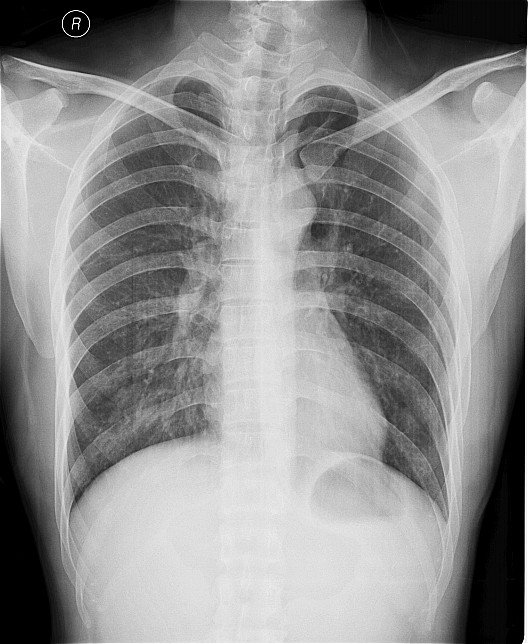

一钨矿工厂因有毒气体泄漏(据说是硝酸)造成十多名工人中毒,均出现不同程度的咳嗽,气逼,心跳加快等中毒症状.其中有几例患者胸片出现小点片状,结节状阴影.是此次中毒引起的肺部改变还是原来就患有矽肺病或其它病变.

肺水肿,及原来就患有矽肺病

原就有的矽肺,未见中毒性肺水肿

支持矽肺,未见肺水肿.建议治疗后复查

矽肺,部分胸片可见肺水肿。治疗复查